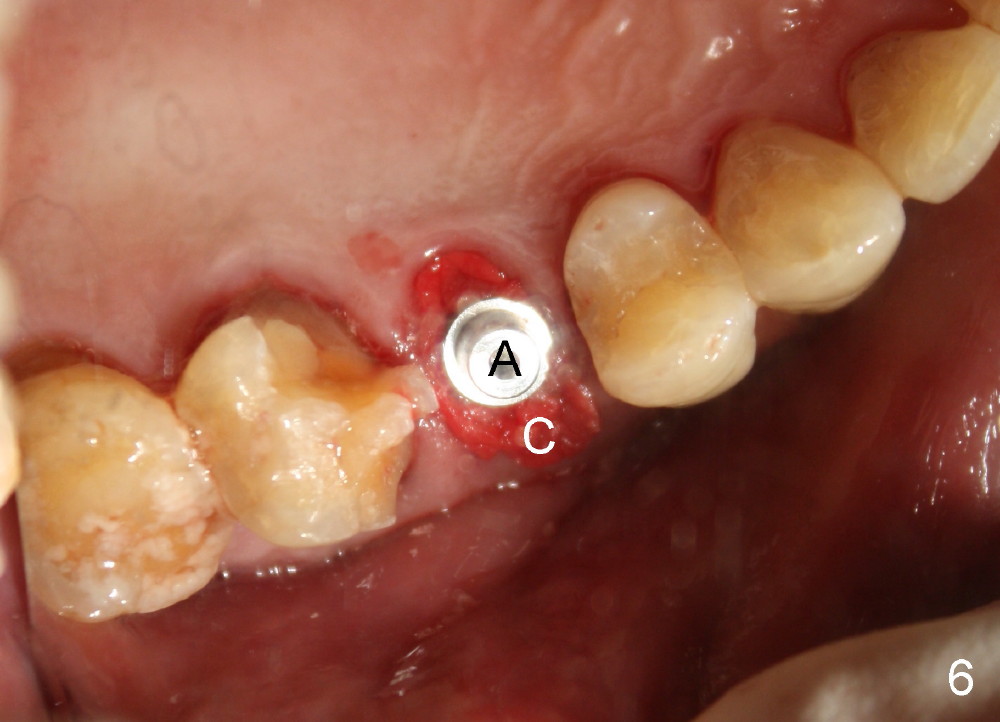

A 72-year-old man is a bruxer with #3 cusp fracture with chronic periapical radiolucency (Fig.1 *) and #4 acute crack. It appears reasonable to take care of emergency (#4 extraction and immediate implant (Fig.3-7: 4.5x20 mm, 45 Ncm)) followed by root canal therapy or extraction for #3. Eight (Fig.8) and 14 (Fig.9-11) days postop, the patient is doing fine and the wound heals normally. But he does not agree any treatment for #3, since it is asymptomatic in spite of a fistula associated with the tooth (Fig.8,9 >). Three months postop, the patient is still asymptomatic and is ready for #4 restoration since the tooth #28 cracks. Follow-up PA shows the persistent distal gap (Fig.12 >, as compared to Fig.4), accompanied with crestal bone resorption (*). Clinically the implant has mild mobility and light tenderness. The patient still refuses #3 treatment. It appears that the implant has failed to osteointegrate. In brief, do not place an immediate implant next to active infection.